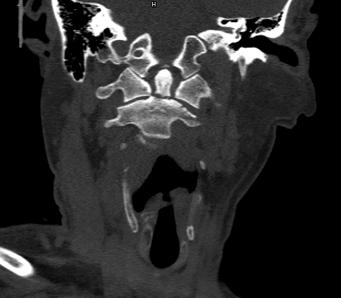

近日,45岁的王先生因高处坠落伤致颈部疼痛、活动受限,于是到北京友谊医院就诊。结合CT结果,医生诊断王先生为枢椎齿状突II型骨折,需手术治疗,王先生被收入骨科病房。

辅助检查显示:颈椎前部可及多发血肿,枢椎齿状突骨折部位向后方移位。

骨科主任医师唐海、单建林两位专家分析患者病情认为,王先生为枢椎齿状突的血运呈双侧雨刷状分布,保守治疗骨折不愈合的风险极大。行内固定手术无疑是最佳的选择,但是手术部位高位颈髓是生命中枢,手术难度极大,对术者的操作要求较高,如有不慎,会给患者带来灾难性后果。经过仔细地考虑,唐海与单建林为患者制定了详细的手术计划,决定实施枢椎齿状突骨折内固定手术。